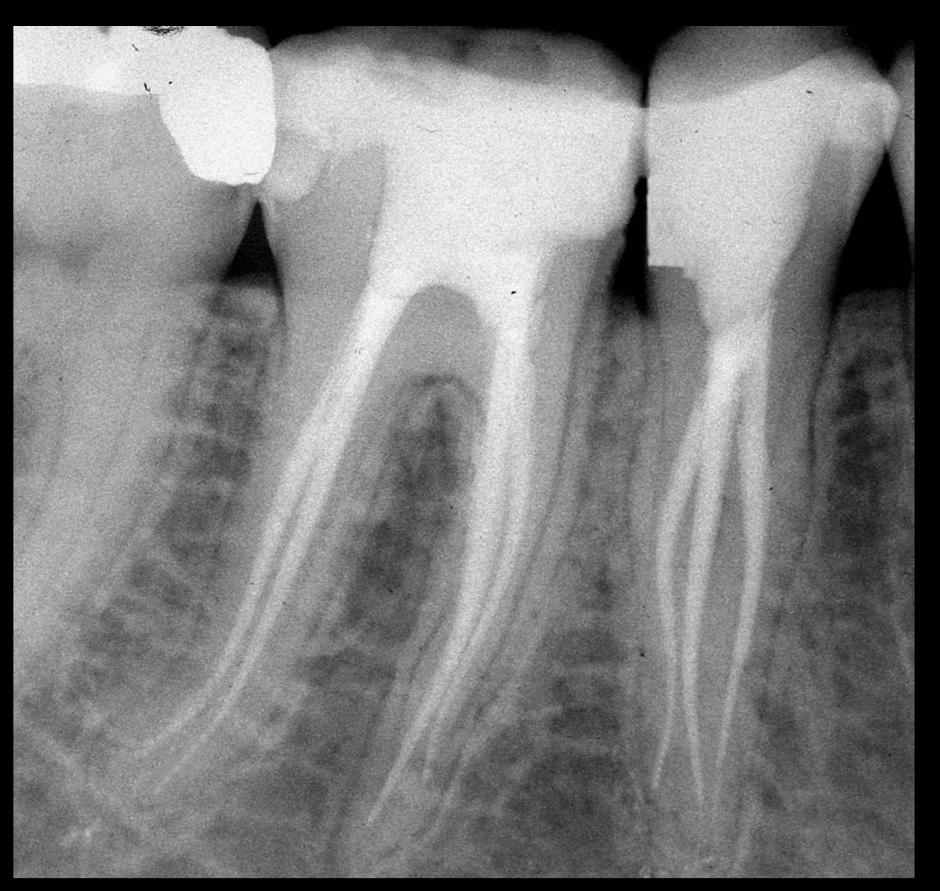

Apertura della corona fino ad arrivare alla camera pulpare (tale trattamento viene eseguito tramite anestesia locale). Si rimuove la polpa e si cercano i canali radicolari del dente, una volta trovati si estirpano i nervi. Si allargano e si puliscono i canali del dente, (tramite strumenti al Nichel titanio o strumenti manuali) prendendo anticipatamente le misure dei canali (per non uscire oltre apice). Si disinfettano i canali e si eseguono vari lavaggi tra un passaggio e un altro per elimininare il fango dentinale. Il medico a questo punto verifica la possibilità di chiudere definivamente i canali o lasciare il dente in prova, inserirendo nei canali un disinfettante e eseguendo una chiusura provvisoria. Al momento di chiudere il dente definivamente, questo viene preparato rieseguendo le misure dei canali da chiudere ed usando per la stessa lunghezza del canale, un cono di guttaperga del diametro necessario. Si scalda il cono in guttaperga e si inserisce nel canale. Durante il trattamento endodondico vengono effettuati una serie di esami radiografici per verificare i risultati, le lunghezze, la forma dei canali.

L'esame radiografico, fondamentale per porre diagnosi in odontoiatria, in endodonzia è irrinunciabile perché è l'unico strumento che ci permette di "vedere" all'interno della radice del dente, è quindi molto importante la possibilità di effettuare lastre con apparecchiature digitali che emettono un quarto della dose di raggi emessa da un radiografico tradizionale e che permettono di conservare la radiografia endorale in una cartella informatica del paziente senza possibili alterazioni nel tempo.